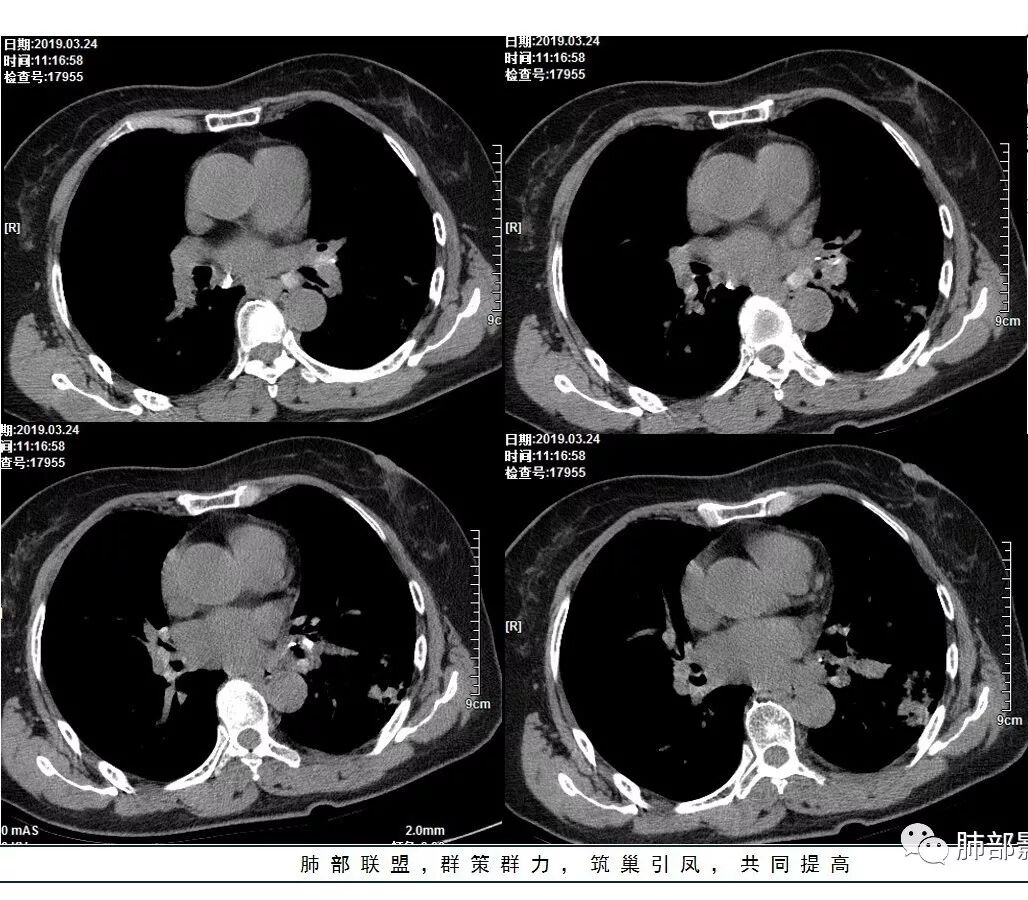

1、主病灶  左下叶斑片状、大片状致密影

2、两肺马赛克灌注

3、两侧肺门区钙化淋巴结

总共就这三大块

2.左肺下叶片状影及多数有边界的结节影,较散,多形性,密度不均(注意许多老师提到这个特点还是比较明显的)。左肺下叶体积未见缩小。

3.病灶强化比较明显。

4.左下叶支气管壁增厚,管腔不均匀狭窄,没有堵塞

5.肺门纵隔见增大钙化淋巴结。提示曾经存在慢性病损可能。